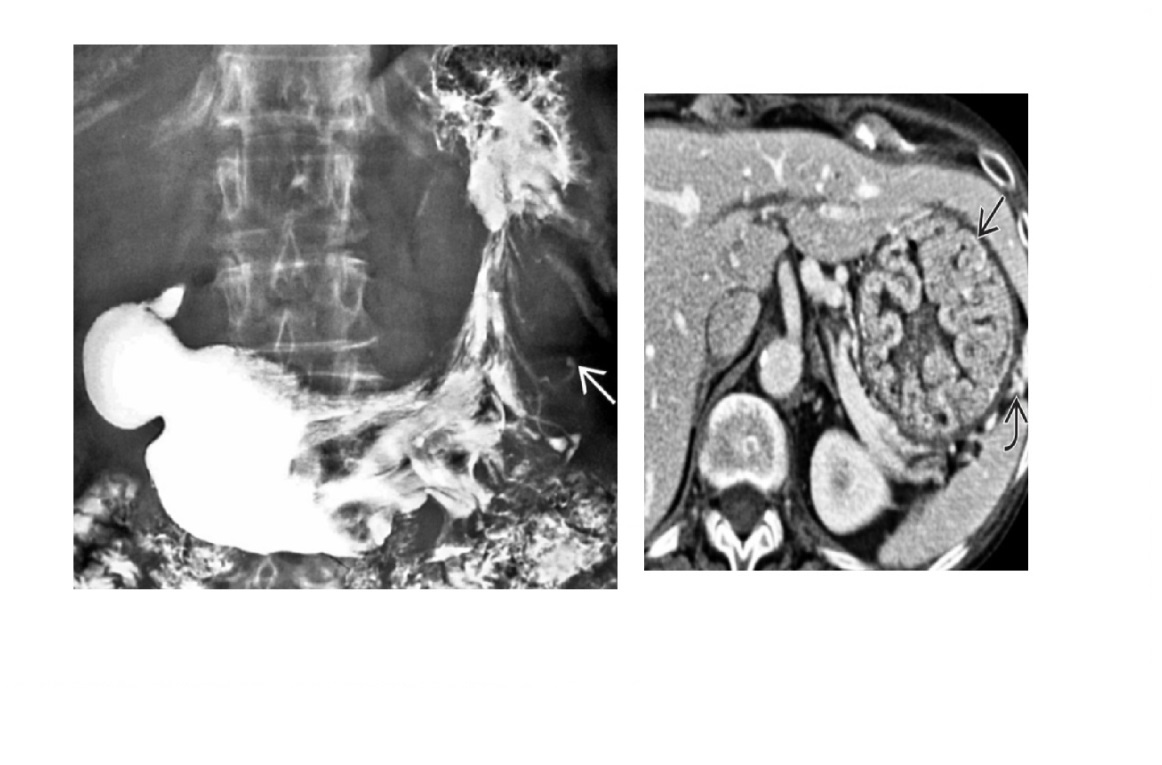

GIST

Well-circumscribed.

**Heterogenous, central necrosis is key **

Hypervascular

submucosal mass extending exophytically from GI tract

Stomach (60%) , dudoenum (30%) and oesophagus (10%)

Remember

- assocaited NF-1

- Carneys triad

- Pulmonary condromas, Exrtra-adrenal paragangliomas, GIST